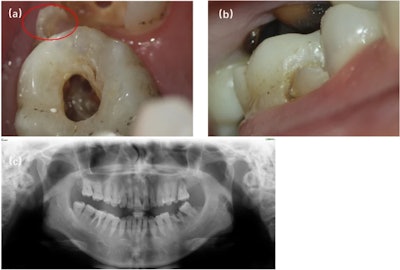

During an oral examination, an eroded cusplike structure was found on tooth #26’s buccal surface. The cusp extended from the cervical edge of the tooth toward the mesiobuccal cusp. The tooth did not respond to an electric pulp and cold test and was preliminarily diagnosed with pulp necrosis, the authors wrote.

(a, b) Preoperative image showing occlusal and buccal planes of the protostylid in tooth #26. The red open circle indicates the protostylid. (c) A panoramic view of permanent teeth with normal anatomy. Images courtesy of Tao et al.

Dental x-rays revealed an extensive periapical radiolucency around tooth #26, but it was unclear whether the protostylid had its own root canal. However, a CBCT image revealed the complex anatomy of the tooth. The pulp chamber of the protostylid was independent in the anterior third of the root and fused with the mesiobuccal root canal in the apical half of the root. Therefore, the patient’s tooth was diagnosed with apical periodontitis, they wrote.